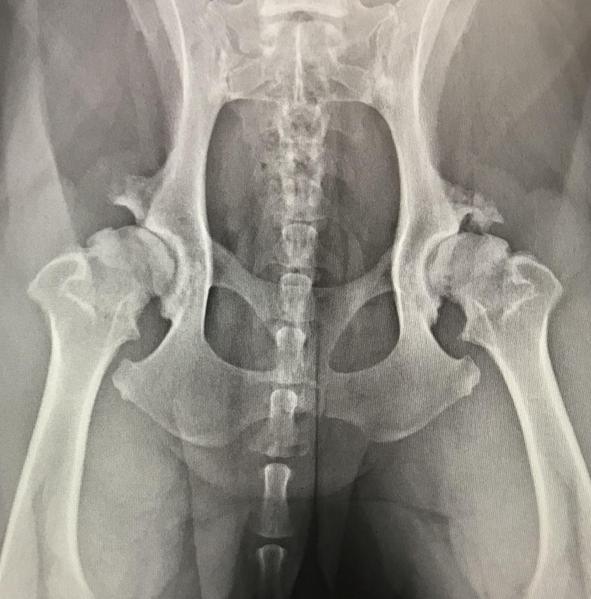

Die Röntgenuntersuchung ist nach wie vor ein unverzichtbares diagnostisches Verfahren, das essenzielle Einblicke in Herz-, Lungen-, Verdauungs- und Harnwegserkrankungen bietet. Besonders bei der Untersuchung des Skelettsystems – ob es sich um Frakturen, degenerative Veränderungen, Wachstumsstörungen oder angeborene Fehlbildungen handelt – ist das Röntgen nach wie vor das Mittel der Wahl.